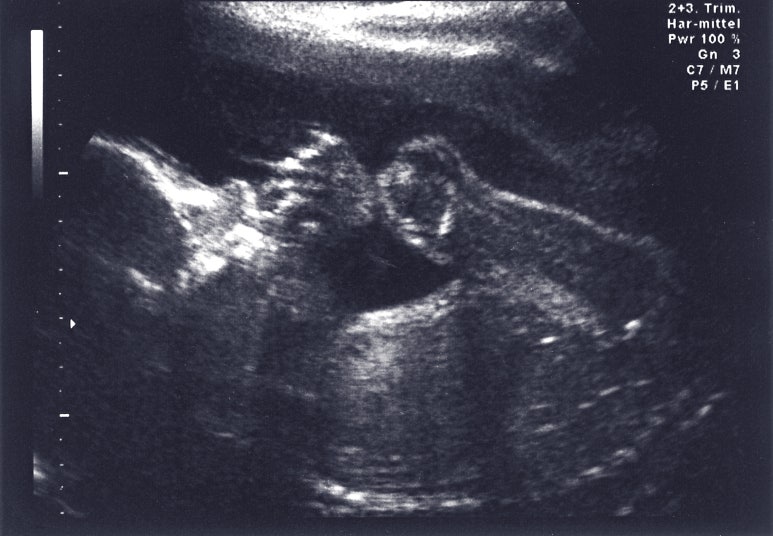

양수란 태아를 감싸고 있는 양막 안에 들어있는 액체입니다.

엄마의 뱃속에서 태아는 이 양수 안에서 생활하죠.

양수는 태아를 외부 충격으로부터 보호하고

태아가 자유롭게 움직일수록 돕습니다.

양수 속에서 활동하며 아기는 자신의 근육과 골격을

자연스럽게 발달시킵니다.

양수는 태아의 성장에 필요한 성분들이 녹아있습니다.

양수의 색은 임신 초기에는 무색이다가

분만할 때쯤 되면 탁해집니다.

양수 안에 태아의 몸에서 나온 물질들이 섞이기 때문입니다.

양수는 엄마의 몸에서 계속 순환하며 교체됩니다.

임신 주수가 늘어날수록 교체 시기도 빠릅니다.

양수의 양은 임신 기간이 지속되면서

늘어나다가 분만이 가까워지면 조금 줄어듭니다.

양수의 양은 일반적으로

임신 초기에는 10~20ml였다가

중기에는 100ml 정도로 늘어나도

하루에 10ml 정도 증가합니다.

임신 후반기에는 1000ml까지 늘었다가

분만이 가까워지면 다시 800ml로 줄어듭니다.